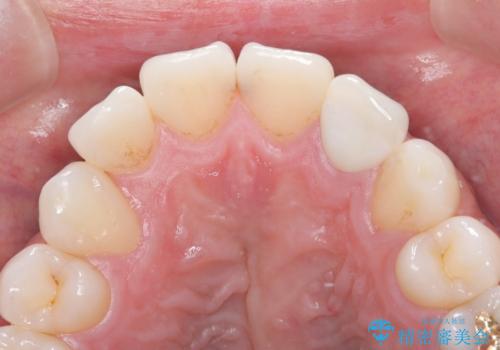

- 「前歯の歯の色が気になる」を主訴に来院された患者さんです。歯の大部分がプラスチックの材料で治療されていました。そこが劣化し変色していたためオールセラミッククラウンで治療を行いました。前歯の色を全体的に白くするために当院でオフィスホワイトニングも行いました。

左上2番の大部分がプラスチックの材料で治療されていました。そのプラスチックの材料が劣化して変色し虫歯になっている状態でした。なので古いプラスチックの材料を全て除去し、その下の虫歯を取った後、オールセラミッククラウンで治療を行いました。オールセラミッククラウンを装着する前に当院にてホワイトニングを行いました。